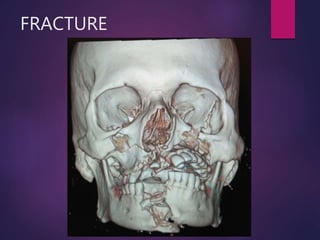

FRACTURE

• #3 Fracture is a break in the structural continuity of bone, And starts immediately after the fracture occurs. fracture results in a well-defined progression of tissue responses that are designed to remove tissue debris, to reestablish vascular supply and to produce a new skeletal matrix.

• #4 Fracture may be a sequel of RTA, fall, interpersonal violence, sports related injury, industrial injury , iatrogenic injury or rbcz of pathology 267

• #11 Energy storage capacity of bone depends upon speed of loading i.e. force of traumatic blow. Higher the speed more the energy stored. When force of traumatic blow overcomes the internal strength of bone fracture occurs. When fracture occurs stored energy is released. Speed of loading affects the pattern of fracture: When loading speed is Low energy dissipated through single fracture line less displacement of soft tissue and remaining intact bone. When loading speed is Higher energy not dissipated thrugh single break Comminuted Fracture and extensive soft tissue damage results